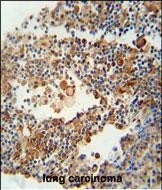

| IHC | 1/100-1/500 | Human,Mouse,Rat |